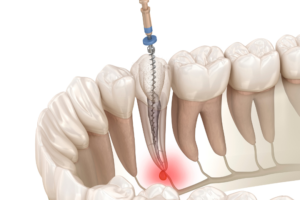

根管治療は、歯の内部に複雑に張り巡らされた根管(神経の管)をきれいにする、非常に繊細で難しい治療です。

その治療の過程で、ごく稀に起こり得る合併症の一つに、「パーフォレーション(Perforation)」があります。

これは、治療中に使用する器具によって、歯の根っこや歯の底の部分に、意図せず穴が開いてしまう(穿孔)状態を指します。

パーフォレーションは、主に以下の二つの段階で発生します。

根管口の探索時

根管治療の際、歯の表面から根管の入り口(根管口)を探す過程で、根管が非常に細かったり、途中で大きく曲がっていたり、以前の治療で詰めた金属(コア)などが残っていたりすると、器具が誤って根管ではない方向に進み、歯の側面に穴が開いてしまうことがあります。

複雑な根管の清掃時

特に、歯の根が二股に分かれる部分(分岐部)や、根管が異常に薄くなっている部分で、感染した壁を薄く削りすぎた結果、穴が開いてしまうことがあります。

また、以前の根管治療でポスト(土台)を入れるために深く削りすぎた部分が、再治療の際に穿孔することもあります。